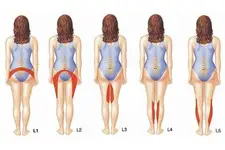

Bel Fıtığı MR ÖzellikleriBel fıtığı, tıbbi literatürde "lumbar disk hernisi" olarak adlandırılan bir durumdur ve omurganın alt kısmında bulunan intervertebral disklerin, çevresindeki dokulara doğru kayması sonucu meydana gelir. Bu durum, genellikle bel ağrısı ve bacaklarda sinir kökü irritasyonuna bağlı olarak çeşitli semptomlarla kendini gösterir. Manyetik Rezonans Görüntüleme (MR), bel fıtığının tanı ve değerlendirilmesinde yaygın olarak kullanılan bir görüntüleme yöntemidir. Bel Fıtığı Nedir? Bel fıtığı, bel bölgesindeki disklerin, normal anatomik yerlerinden kayarak sinir köklerine baskı yapması sonucunda oluşan bir durumdur. Bu durum, genellikle şu şekillerde ortaya çıkabilir:

Bu durumlar, belde ağrı, bacaklarda uyuşma, karıncalanma ve güçsüzlük gibi çeşitli semptomlara yol açabilir. MR Görüntüleme Yöntemi Manyetik Rezonans Görüntüleme (MR), vücut içindeki dokuların ayrıntılı görüntülerini elde etmek için manyetik alanlar ve radyo dalgaları kullanan non-invaziv bir görüntüleme tekniğidir. MR, yumuşak dokuların görüntülenmesinde X-ışınlarına göre daha üstün sonuçlar verir. Bel fıtığı gibi durumların tanısında oldukça etkili bir yöntemdir. Bel Fıtığı MR Özellikleri Bel fıtığı MR görüntülerinde dikkate alınması gereken bazı önemli özellikler şunlardır:

Bel fıtığı tespit edilse bile fizik muayene sonuçlarıyla çelişiyorsa, bu durum hastanın tedavi sürecini olumsuz etkileyebilir. Yanlış bir tıbbi değerlendirme, hastanın yanlış bir tedavi almasına neden olabilir. Bu nedenle, klinik bulgular ile görüntüleme sonuçlarının birlikte değerlendirilmesi son derece önemlidir. Tedavi planı, her iki verinin bir arada göz önünde bulundurulmasıyla daha sağlıklı bir şekilde oluşturulmalıdır.